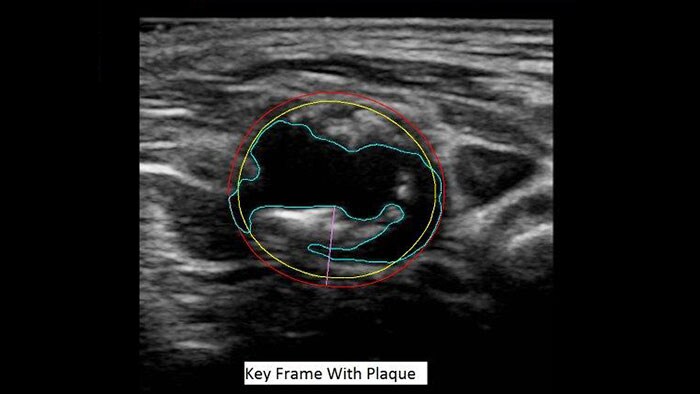

US Q-App Vascular Plaque Quantification (VPQ)

A novel measurement of atherosclerotic plaque volume

US Q-App Vascular Plaque Quantification (VPQ) helps you perform comprehensive volume analysis for carotid plaque; a significant indictor in cardiovascular disease. Automatically measure plaque composition throughout a captured volume, percent area vessel reduction and other characteristics using 3D technology. Results may be posted to patient exams.

Benefits

- 3D technology to visualize and quantify vascular plaque.

- Streamlined workflow through protocol-based task guidance.

- Automatically calculates and displays vessel and plaque boundaries for each frame in the volume data.

- Analysis data presented on image.

- Total plaque volume calculated (mm3).

- Maximum % area reduction calculated.

- Graph analysis data (lumen area, plaque area, reduction over vessel length.

- Compatible with the Philips EPIQ, Affiniti and iU22 systems, monochrome, single-volume 3D volumes acquired with the VL13-5 mechanical transducer.